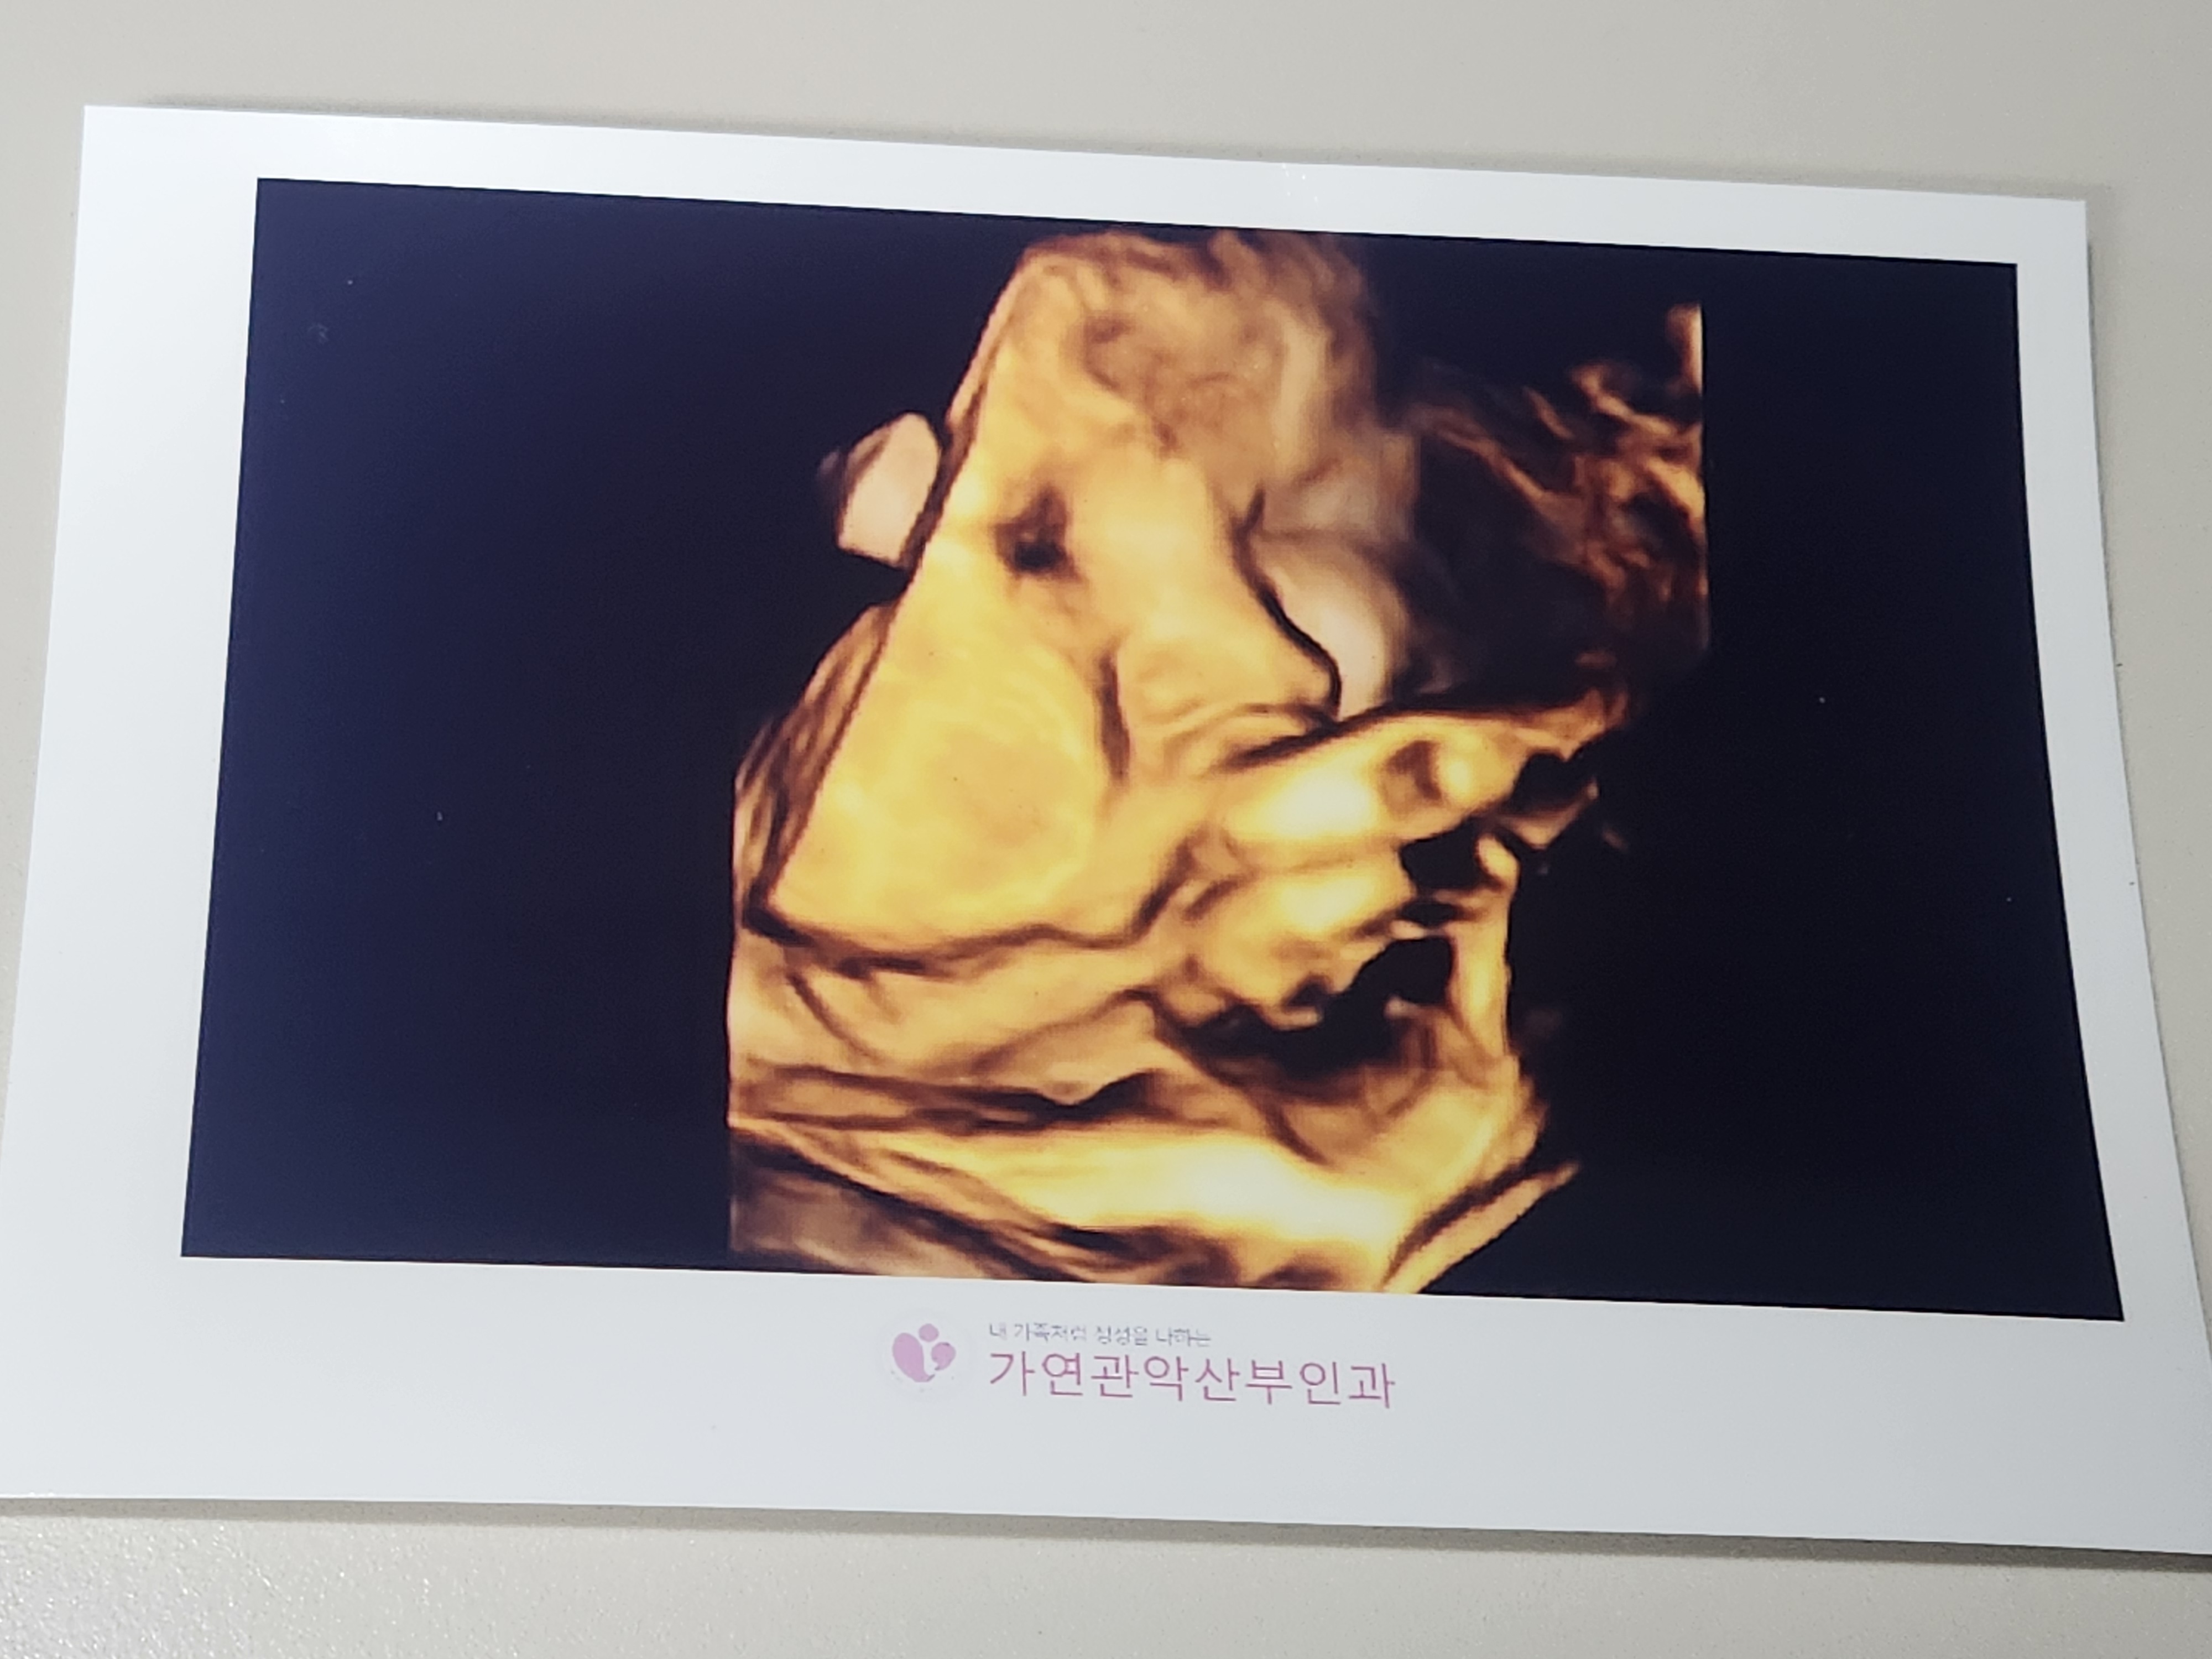

태동검사가 끝난 후 초음파 검사를 했습니다.

또 얼굴을 가린 복덩이지만, 그 사이에 볼살이 귀여워진 복덩이입니다.

초음파 검사상 자연분만 하기에 상태도 아주 좋다고 하셨습니다.

태아는 37주에 2.5kg이었으며, 원장님께서 37주 이상 2.5kg이상이면 지금부터 언제나와도 정상분만이라고 하셨고, 언제나와도 이상하지 않은 주수라고 마음에 준비를 하시라고 말씀해주셨습니다.